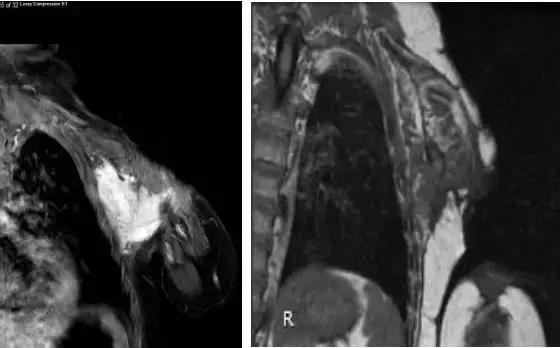

美国时间3月28日在线的权威肿瘤学杂志柳叶刀上又传来传奇抗癌药larotrectinib(LOXO-101)的最新研究数据!此次该药在部分儿童癌症患者达到了93%的治疗应答!其中,有两位儿童纤维肉瘤患者,用药之后肿瘤缩小,随后进行了手术切除,停药4.8个月和6个月之后,肿瘤没有复发,也似乎看到了“治愈”的希望。

2岁纤维肉瘤治疗前,治疗5周期后